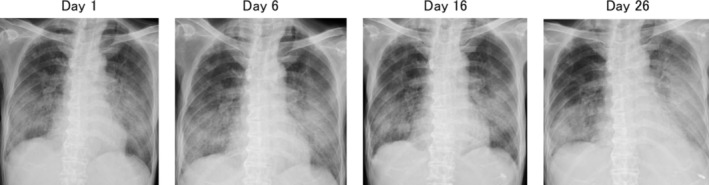

免疫检查点抑制剂(ICIs)是肺癌的基本治疗方法,但其在同种异体造血干细胞移植(alloo - hsct)后的安全性尚不清楚。我们报告一例66岁的男性,因急性淋巴细胞白血病而接受脐带血移植,后来发展为肺腺癌。开始了派姆单抗单药治疗,但患者出现了严重的类固醇难治性免疫相关肺炎,导致治疗开始56天后死亡。鉴于既往HSCT的肺癌患者使用ICI的报道很少,本病例强调了关键的安全性考虑。

Immune checkpoint inhibitors (ICIs) are essential treatments for lung cancer, but their safety following allogeneic haematopoietic stem cell transplantation (allo-HSCT) remains unclear. We report a case of a 66-year-old man who underwent umbilical cord blood transplantation for acute lymphoblastic leukaemia and later developed lung adenocarcinoma. Pembrolizumab monotherapy was initiated, but the patient developed severe steroid-refractory immune-related pneumonitis, leading to mortality 56 days after treatment initiation. Given the scarcity of reports on ICI use in lung cancer patients with prior HSCT, this case highlights critical safety considerations.